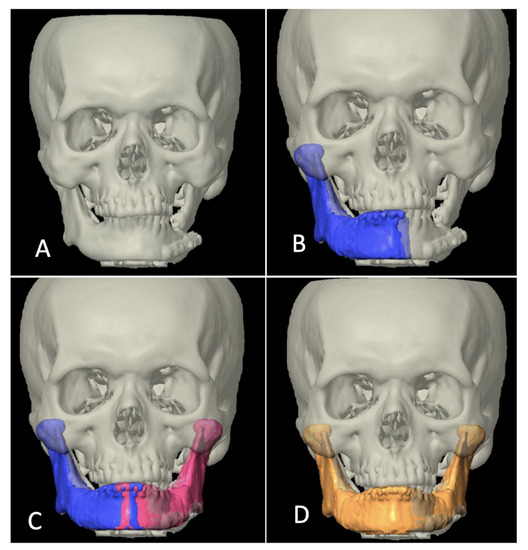

Category III included the cases where defect crossed the midline, but since primary surgery was carried out elsewhere, previous imaging data were not available. In those cases, the authors’ institution’s radiology data bank was manually searched for the mandibular anatomy that most closely mimicked the patient’s mandible in consideration for reconstruction. The inter-condylar dimension was taken as a reference for transverse dimension whereas a normal value of FH-NPog angle (angulation between Frankfort horizontal plane and Nasion-Pogonion line) was taken as a sagittal reference to look for a close match. It was also made sure that the mandibular arch form of the chosen data grossly coordinated with the maxillary arch form of the patient, i.e., in class I skeletal relation (Figure 4).

Figure 4.

Designing template in category III. (A) 3-dimensional view of defect. (B) Appropriate mandibular anatomy selected from radiology data bank taking intercondylar distance as horizontal reference (red color). (C) Frankfort Horizontal Plane (FHP)-Nasion Pogonion (NPog) angle used as sagittal reference (87 ± 4 degrees being the normal range). (D) Arch form coordination approximately matched with maxilla. (E) Condylar anatomy of database matching the patient’s original condylar anatomy (red).